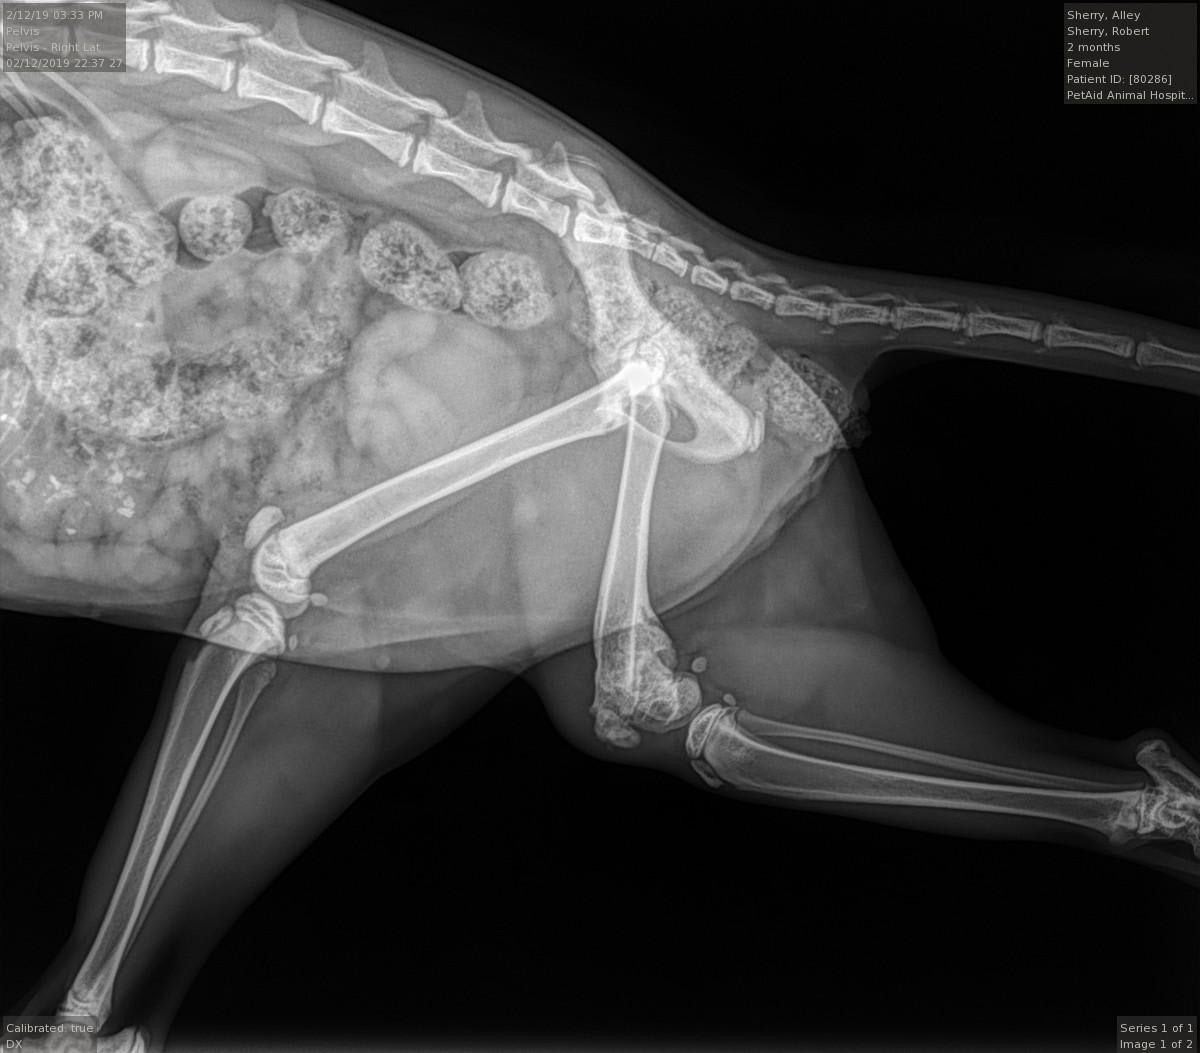

I rescued a young cat (aprox 4 months old) that had a bad limp while walking. Upon taking her to the Vet I discovered that she had her back left leg broken badly while very young and it had never been set (see X-Rays). The vet is recommending amputation. I would like another opinion. She runs, jumps, plays and sleeps on her left side, but limps badly walking. Thank You..